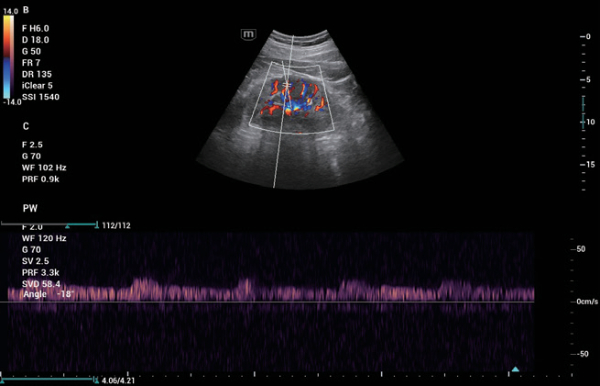

ZST+ ??? ???? ?? ???

ZST+ ???? ???? ??? ???? ??? ?????. ??? ???? ?? ? ???? ?? ??? ?? ??? ?????. ??? ??? ? ?? ??? ??? ???? ?????? ??? ???? ???? ??? ?? ?? ?? ?? ???? ?? ??? ?? ??? ?????.